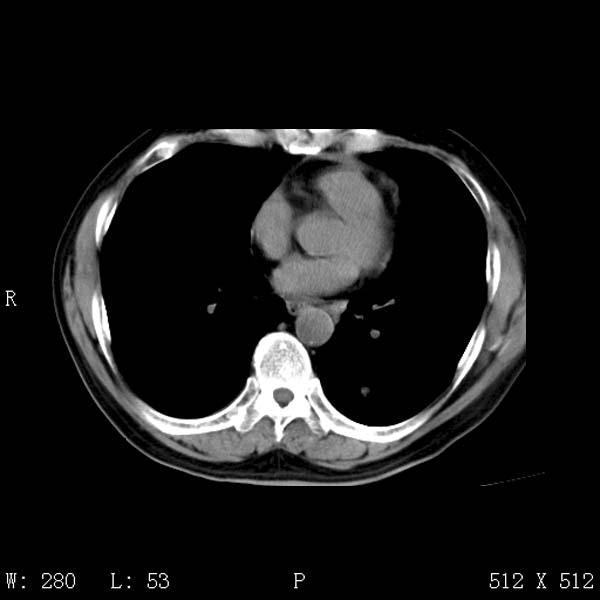

以下是引用守望可可西里在2008-6-24 1:11:00的发言:[br][br] 考虑为周围型肺癌:[br] 1.分叶结节,形态极不规则,蟹足样伸展的恶性浸润特征比较明确。[br] 2.磨玻璃影中由多个更高密度小结节聚集呈梅花瓣样。[br] 3.局部胸膜凹陷征比较明确。[br][br] 另:纵隔胸膜明显增厚、粘连。

以下是引用zjzjr在2008-6-24 11:19:00的发言:[br]支持左下肺周围型肺癌伴右肺转移,纵隔淋巴结转移,心包积液.

以下是引用zhangling在2008-6-24 14:56:00的发言:[br]我们科室意见报告为[br][br]1考虑左下肺周围型肺癌[br]2右肺小结节考虑转移瘤,纵隔淋巴结转移[br]3心包积液. [br] 各位老师分析的相当好 谢意[br]